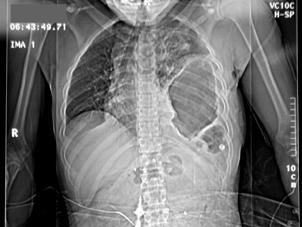

Fracturi costale multiple Hemitorace drept strivit

Volet costal si hemotorace

drept Fracturi costale multiple

Volet costal si hemotorace drept

Hemitorace drept strivit Hemitorace drept strivit Hemitorace drept strivit